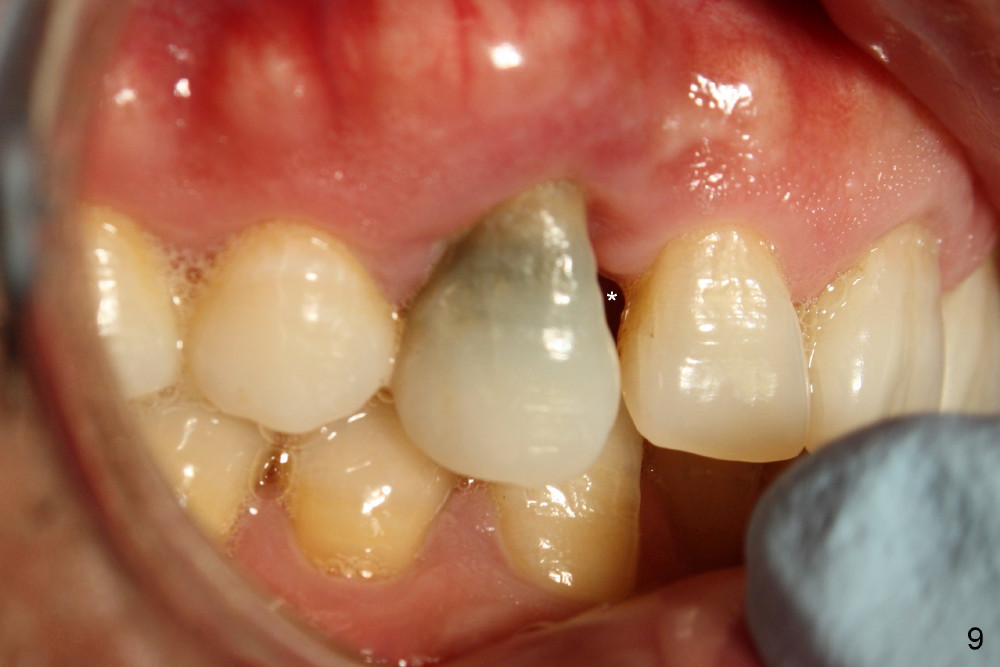

A male patient had trauma to the tooth #6 at the age of 13.  The affected tooth has remained asymptomatic for more than 30 years (Fig.1).   X-ray reveals an oblique root fracture (Fig.2 >) with radiolucency in the mesial alveolus (*, apparently normal trabecular pattern).  Six years later (Feb. 2011), an acute infection develops (Fig.4 *).  It requires incision & draining and antibiotic.  At that time, the trabecular pattern disappears around the fracture line mesially (Fig.3 *).  Four months later cone beam CT shows bone loss between #6 and 7 (Fig.5 *).  Root canal therapy is done as a palliative measure (Fig.6 R; C: Cavit).  Three months later, MTA (mineral trioxide aggregate) is placed in the coronal canal next to the fracture line (Fig.7 M).  It is hoped that MTA can promote nearby bone and cementum to regenerate to seal the fracture line.  Four months after MTA application, there is no sign of bone regeneration (Fig.8).  Bone is lost for approximately 7 mm.

The tooth is discolored probably due to the side-effect of MTA(Fig.9; photo taken 9 months post-MTA).  The mesial gingiva recedes (*).  There is mild persistent pain with purulent discharge mesiobuccally (Fig.10 >).  The corresponding pocket remains 7-8 mm deep in spite of root canal therapy and MTA.